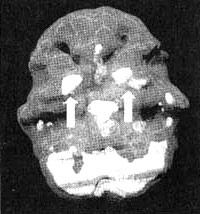

Система базальных ганглиев

Иллюстрация к книге — Измените свой мозг - изменится и жизнь! [i_036.jpg]

Трехмерное изображение — активный мозг, вид снизу.

Базальные ганглии — это комплекс крупных образований, расположенных в центральной части мозга окружающих центральную лимбическую систему.

Базальные ганглии участвуют в процессах интегрирования чувств, мыслей и движений, а также в регулировании моторной функции. Базальные ганглии задают наше у организму режим, а котором он работает а состоянии покоя или уровень тревожности. Кроме того, они способствуют модулированию мотивации и, по всей вероятности, отдают за ощущения удовольствия и экстаза. Рассмотрим каждую из этих функций более подробно.